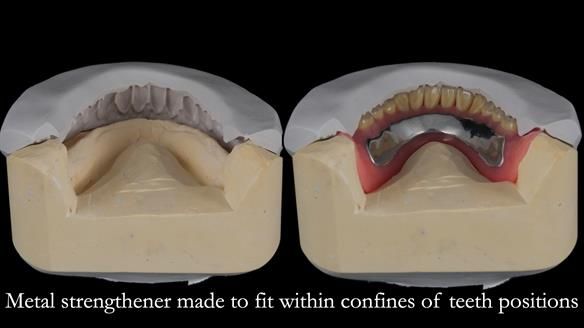

Welcome to Newsletter 62. In this edition, I walk through the process of removing 5 upper anterior teeth, adding to an existing upper RPD, followed by creating and fitting metal based complete dentures for Rafique, a 71 year old man.

The detailed clinical situation and treatment process are outlined below, with clinical work provided by me and technical work by Rowan Garstang. The treatment spanned 12 months, involving removing 5 upper anterior teeth, adding to an existing upper RPD, followed by creating and fitting metal based complete dentures.